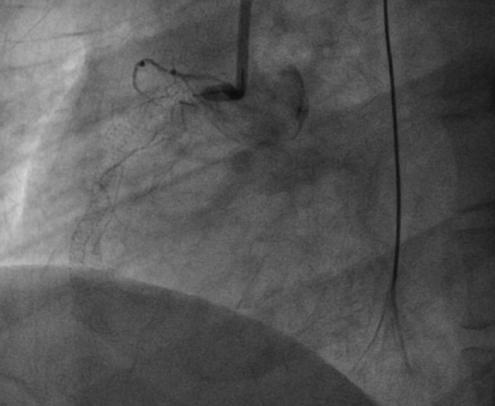

患者李先生,41岁,既往因反复胸痛1月余,就诊于当地医院,就诊时突发意识丧失伴休克血压,予以ECMO辅助下成功行右冠PCI治疗后,患者病情稳定。出院后未规律服用阿司匹林及替格瑞洛药物,7天前再发心前区疼痛不适,再次就诊当地医院行冠脉造影示:右冠近段支架内闭塞,予以冠脉内血栓抽吸及溶栓治疗后,右冠血流仍未能恢复。经当地医院治疗一周后转入中南大学湘雅三医院心内科,复查冠脉造影示:右冠支架内完全闭塞(图1)。经科室讨论后,认为传统冠脉内抽栓及溶栓无法解决该患者的顽固性机化血栓问题,决定采用目前治疗冠脉机化血栓最先进的技术—准分子激光消融导管(ELCA)进行治疗。

图1.右冠支架内完全闭塞